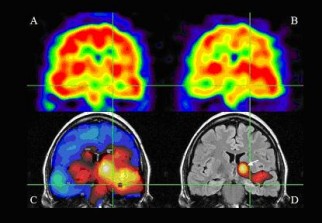

A l’occasion de la journée mondiale de l’épilepsie, des portes ouvertes de sensibilisation à cette pathologie seront organisées jeudi à la Medina Center Ardis (Alger). Des spécialistes en la matière seront présents afin de donner des conseils aux malades et aux parents.L'épilepsie est une maladie neurologique chronique, provoquée par des dysfonctionnements de l'activité électrique du cerveau se manifestant par des convulsions.